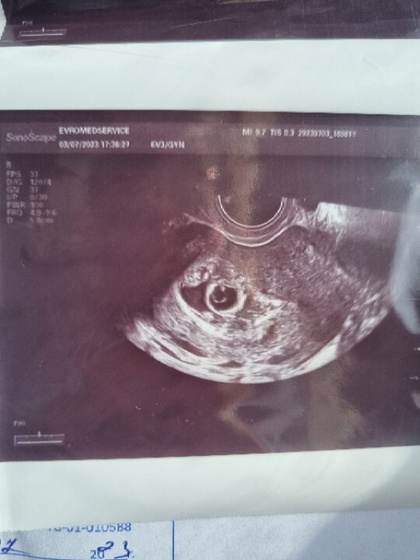

На фото видно пузырëк внутри плодного яйца. Это желточный мешок. От него малыш питается. Как мне говорила моя узистка, если желточный есть, то и эмбрион есть, просто ещё очень маленький, не разглядеть. Через неделю будет видно его и сердечко.

По УЗИ вроде видно желточный мешок, могу и ошибаться.